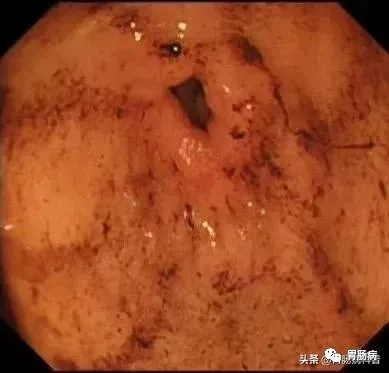

在食道入口,距門齒約18至20cm處可見片狀黏膜剝脫及條索狀裂傷,持續(xù)滲血。

此時終于查明消化道出血原因,為患者的下一步治療指明方向。

追問患者病史,原來是患者因關(guān)節(jié)腫痛,長期口服強的松及去痛片,昨日晚餐時進食的自家做的干餅子,夜間即出現(xiàn)嘔血,今日又再次大量嘔吐暗紅色血液2次,遂急診入院治療。